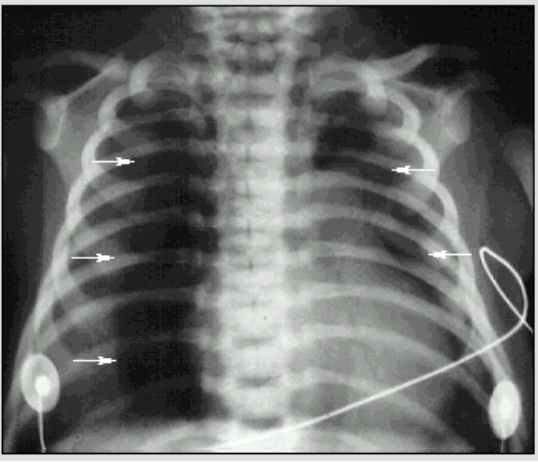

生后第一天

纵隔气胸:

胸部X线检查:

纵隔气胸(箭头)

正中线两边透亮度增加

将肺挤至外周